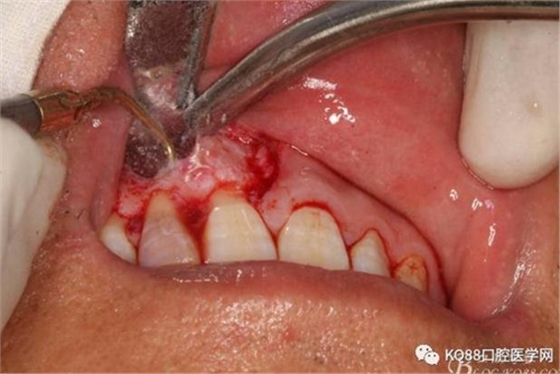

圖6.行唇側(cè)角形切口(11近中垂直切口+齦溝內(nèi)水平切口)垂直切口距離前庭溝約1~2mm。這樣可以減輕術(shù)后腫脹。

圖7. 角形切口中的齦溝內(nèi)切口情況:11號(hào)刀片伸進(jìn)齦溝內(nèi)斜切。

圖8.從垂直切口和水平切口的連接處翻瓣。發(fā)現(xiàn)11和12之間的骨壁有缺損。